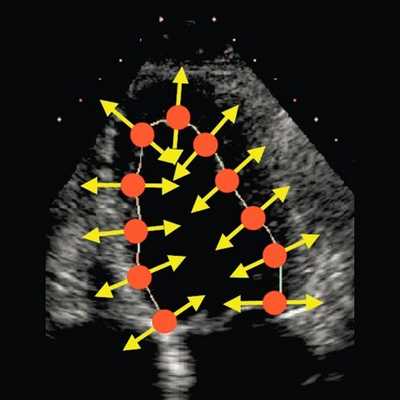

В настоящее время бурное развитие современных ультразвуковых технологий привело к появлению совершенно иных подходов к оценке функционального состояния сердца, которые на очень ранних этапах заболевания позволяют выявлять минимальные нарушения функции сердца. Мы еще не успели должным образом изучить возможности тканевой допплерографии, как появилась еще одна методика, получившая в англоязычной литературе название - speckle tracking. В отличие от тканевой допплерографии, основанной на эффекте допплера, speckle tracking основан на определении скорости движения миокарда при помощи отслеживания перемещения естественных акустических маркеров - пятнистых структур, на стандартном эхокардиографическом изображении в В-режиме (рис. 1).

Рис. 1. Оценка скорости движения миокарда при помощи отслеживания перемещения естественных акустических маркеров - пятнистых структур, на стандартном эхокардиографическом изображении в В-режиме.

Суть метода заключается в том, что акустические маркеры случайным образом равномерно распределяются по всему миокарду. Размер каждого пятна составляет от 20 до 40 пикселей (точек). Положение каждого пятна определяется и точно прослеживается на последовательных кадрах. Таким образом, можно определить расстояние, на которое перемещается пятно от кадра к кадру. Зная частоту смены кадров, можно определить скорость движения пятна. С целью повышения качества отслеживания пятнистых структур применяется высокая частота смены кадров - 60-100 кадров в секунду. Особенности движения сердца, вращение в грудной клетке, а также дыхательная экскурсия грудной клетки могут приводить к смещению пятен из плоскости сканирования. Однако эти изменения не успевают произойти в значимом количестве между двумя последовательными кадрами. Таким образом, по движению пятнистых структур можно получить данные о скорости, деформации и скорости деформации всех участков миокарда. Техника вычисления деформации по двухмерному изображению значительно проще, чем при использовании тканевой допплерографии, так как при этом отсутствуют ограничения, связанные с параллельностью движения объекта и ультразвукового луча. Для последующих вычислений достаточно одного сердечного цикла (рис. 2). Обработка ультразвуковых изображений проводится в режиме offline [2].